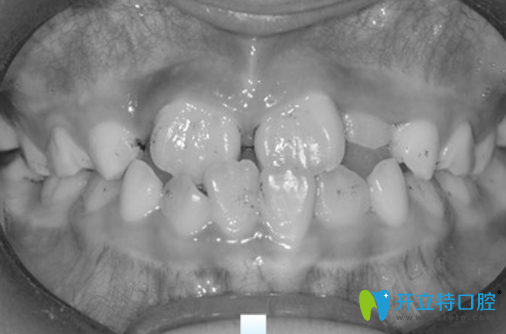

兒童反頜矯正半年后牙齒變化圖:

在成都金琴口腔找許楨睿做兒童反頜矯正半年后

之后我們差不多一個星期復查一次,大概半年左右,兒子的矯正終于結束了,反頜解除啦,心里非常高興。